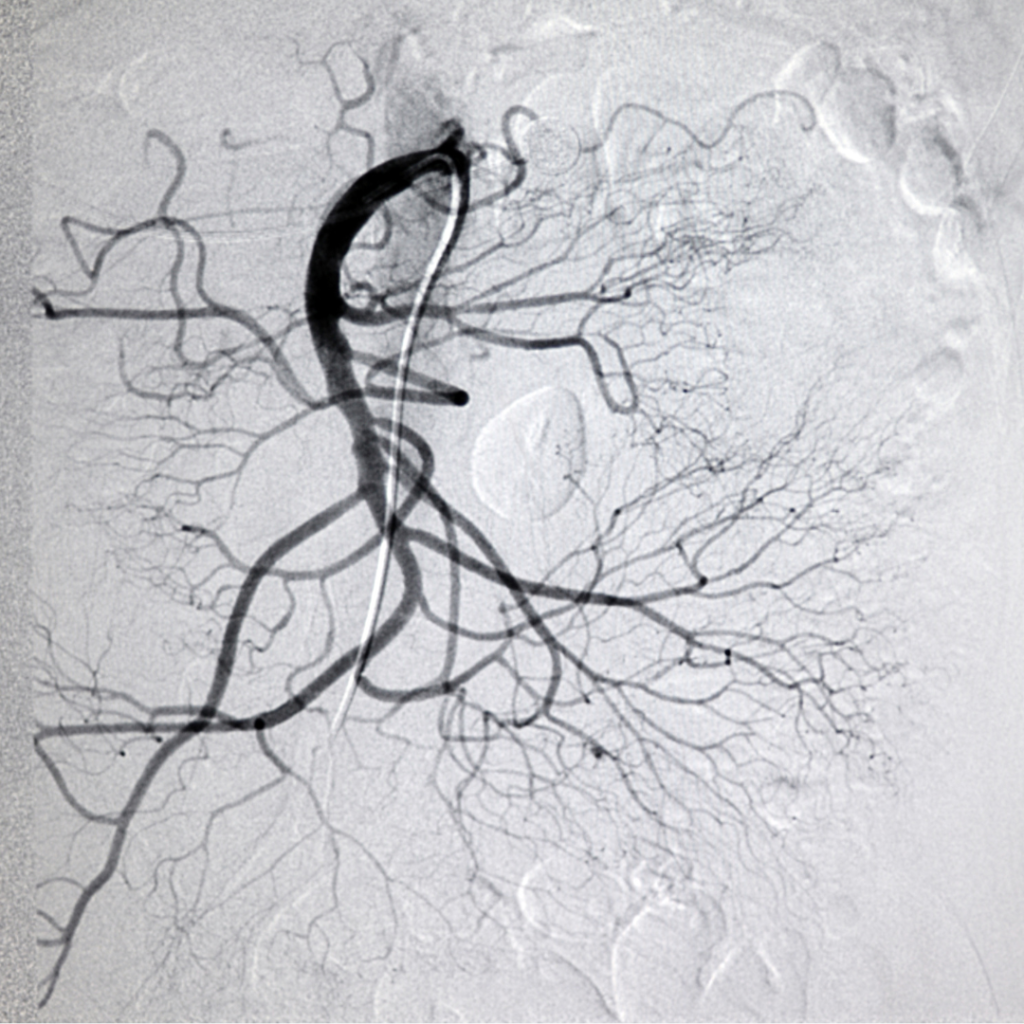

Los pacientes con síndromes coronarios agudos requieren un manejo inmediato de su enfermedad cardíaca antes de cualquier evaluación preoperatoria debido a la alta probabilidad de complicaciones cardiovasculares durante el período…